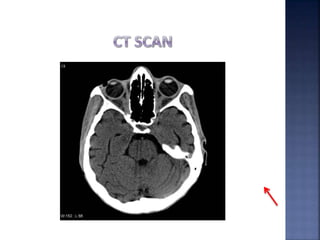

• OM 150 and 300

• CT (axial/coronal) 3-5mm slices

• 3D CT

• MRI + 3D Reconstruction

• Co-localization of CT on MRI

• Sinuscopy

• Computer assisted planning and surgery